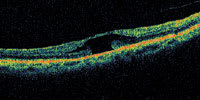

| Figure 2. There is subretinal fluid beginning to form under the central fovea in what may represent a prehole condition. No full-thickness defect can be observed in any cut. |

A central clinical challenge has been accurately diagnosing early macular holes which may be mimicked by many other conditions.34,35 No imaging modality has enhanced our diagnostic capability more than the OCT; superior imaging capabilities have improved diagnostic accuracy, clinical monitoring, and postoperative assessment.36-38 The OCT unequivocally demonstrates early stages of full-thickness macular holes (Figure 1), and allows distinction of pseudohole and pre-macular hole conditions in almost all instances. Fluid accumulation in early, presumed pre-macular hole stages have been corroborated by OCT observations (Figure 2). Serial images have been reported showing the progression from apparent impending macular holes to full thickness macular holes.39-42 It has depicted many other configurations that might be in the spectrum of lamellar or pre-macular hole conditions (Figure 3 and 4).